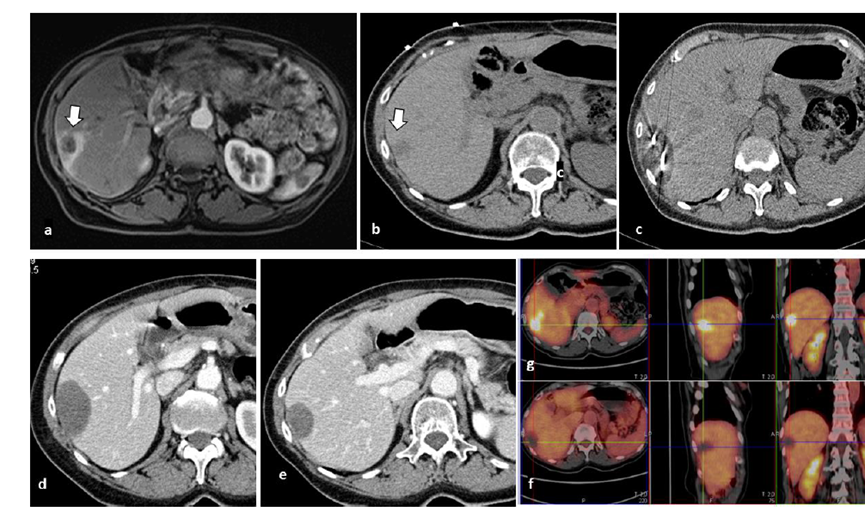

79 歲男性,肝轉移(結直腸癌)腫瘤的完全消融病例

( a ) 軸向 MRI 和 ( b ) 軸向 CT 顯示肝S8段有一個16mm的病灶,鄰近肝緣。( c )冷凍消融期間CT顯示放置了2個冷凍探針,低密度冰球包圍病灶。(d)術后1個月隨訪 CT顯示冰球對應的壞死區(qū)域,未見復發(fā)。(e)術后6個月的CT,壞死區(qū)域縮小,未見復發(fā)。(f)與基線影像(g)相比,12個月后的FDG-PET/CT顯示未見FDG攝取。

(a)軸向CT顯示病變位置毗鄰心臟和上腔靜脈(黑色箭頭)。1個月后的軸向(e)和冠狀位(f)增強CT掃描顯示低密度區(qū)域,由于肉芽組織反應引起的邊緣增強。